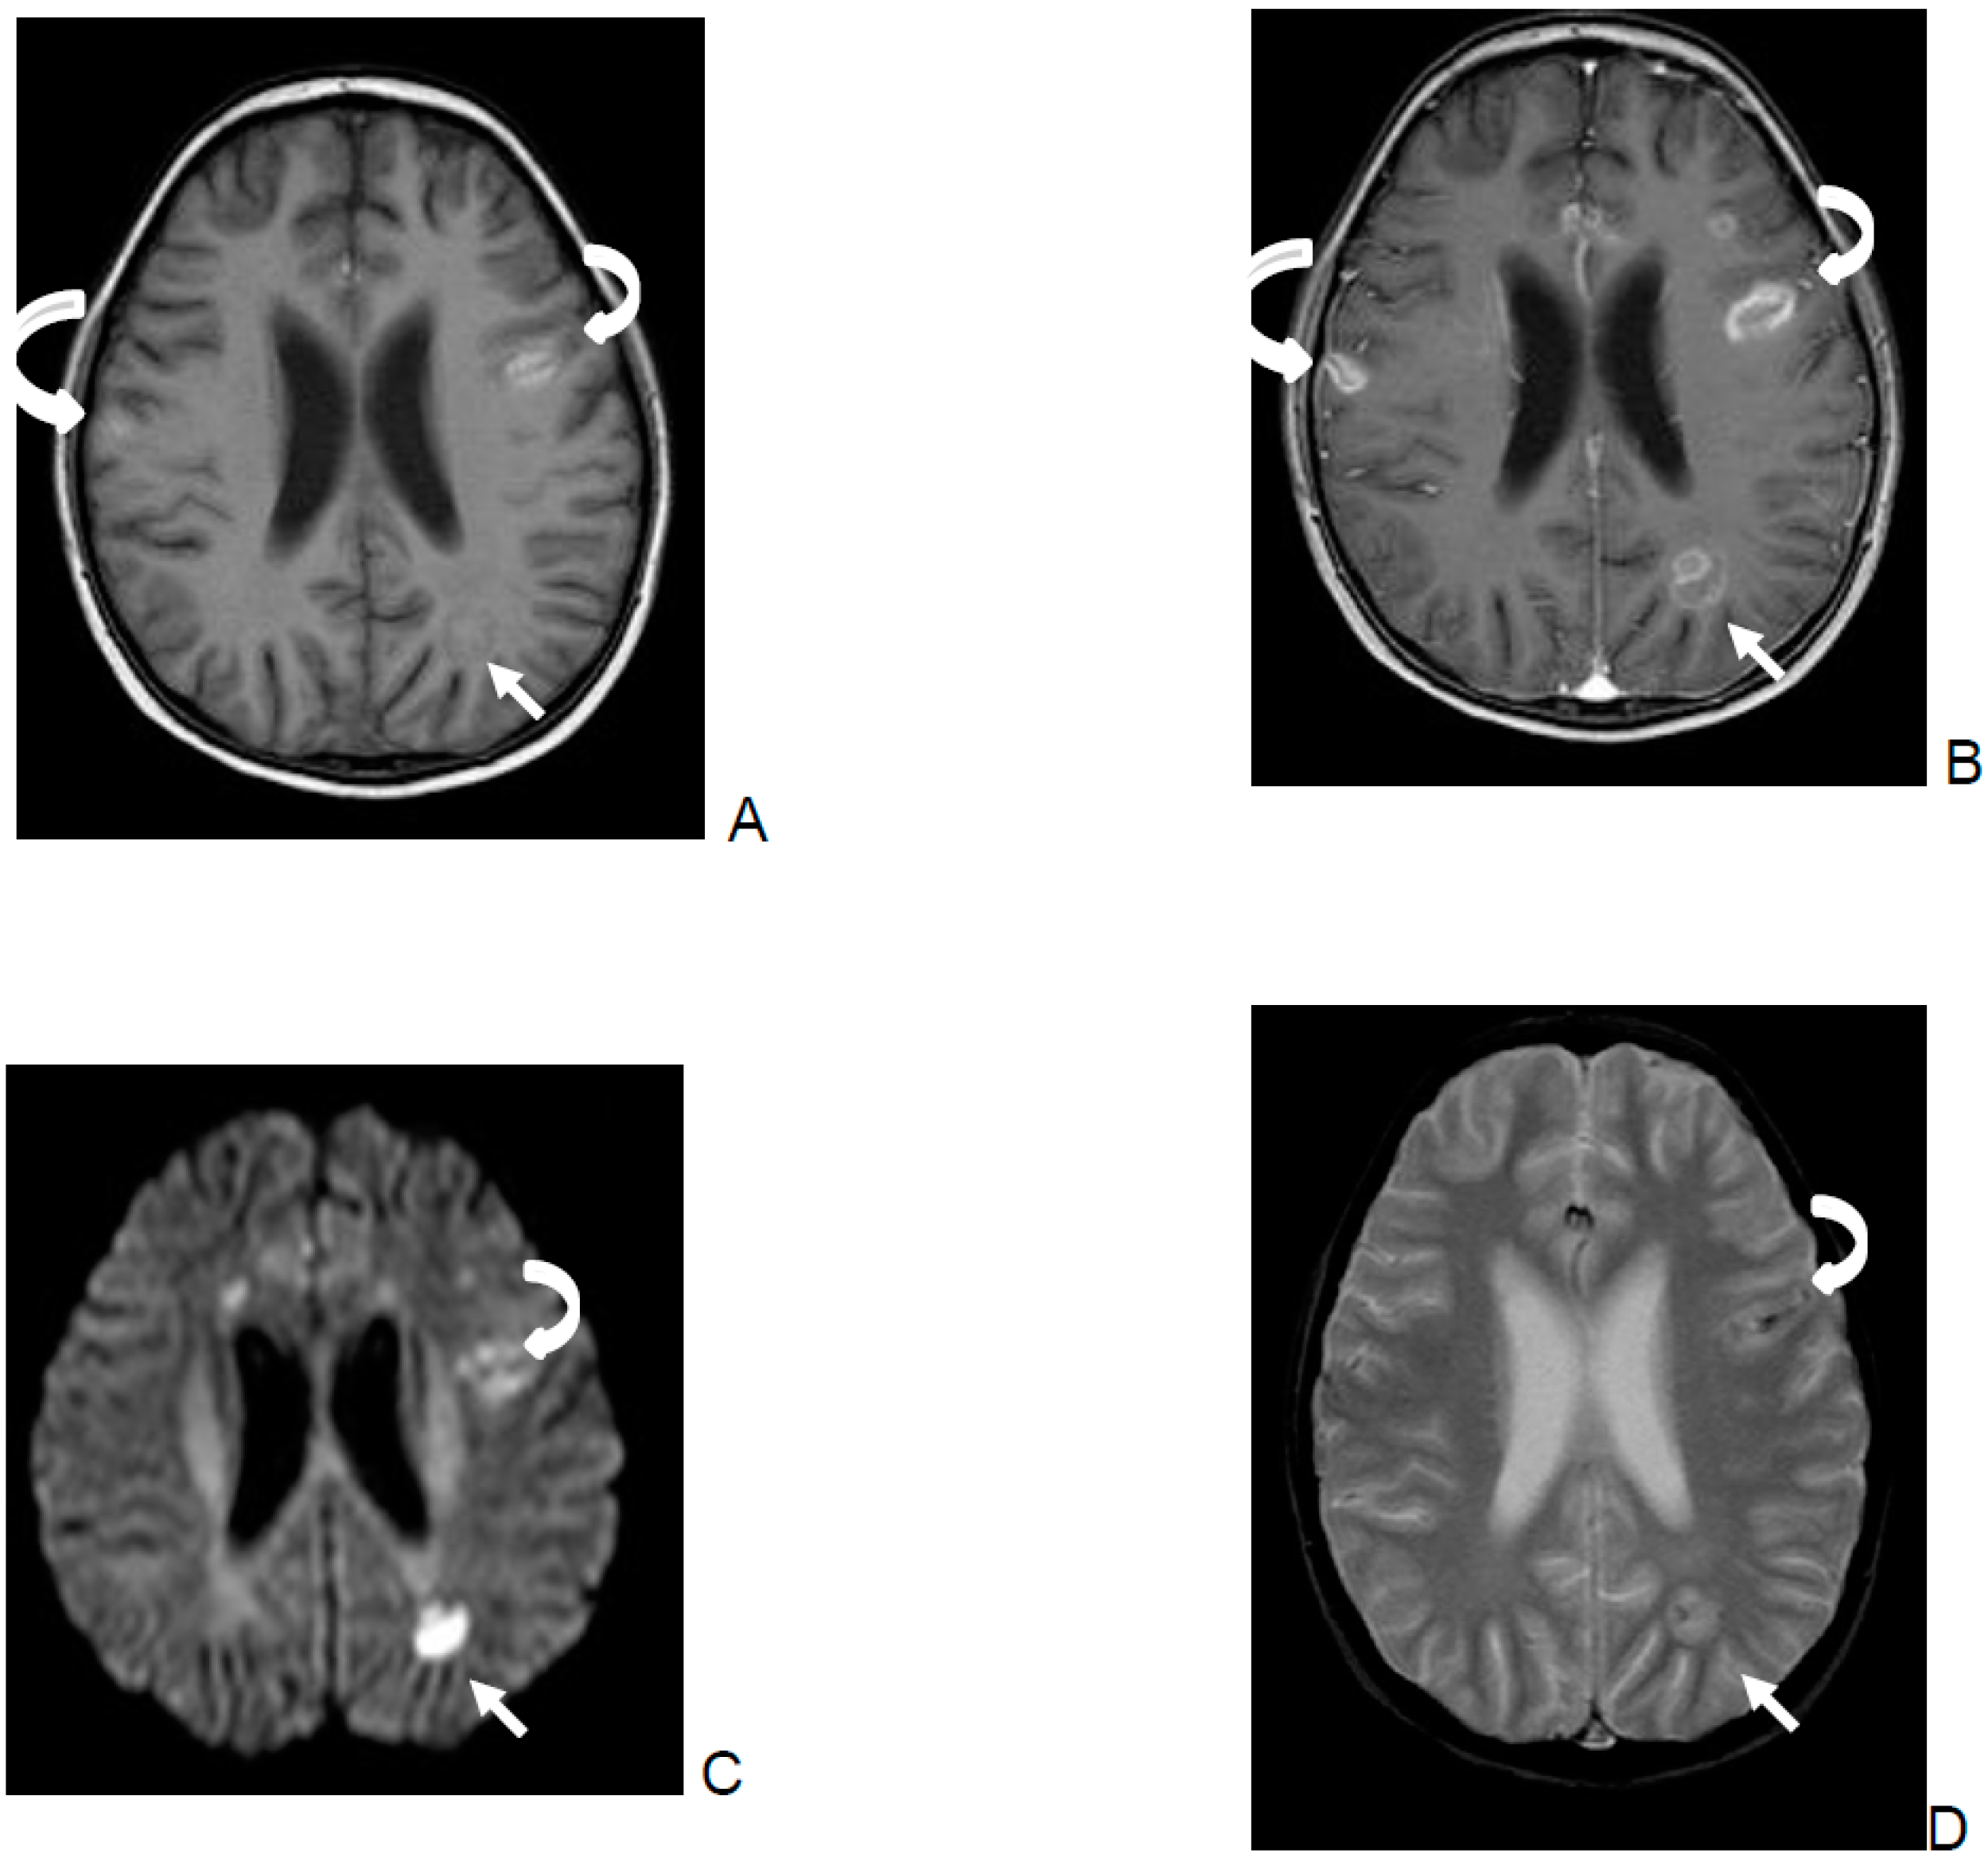

- Focal or multifocal involvement as well as the type of enhancement on T1 images after contrast were evaluated.

| Outcome | Parenchymal Multifocal (Lobes) | Parenchymal 1 lobe | Enhancement Ring-Like | Enhancement Nodular | Enhancement Subependymal No Ventriculitis | Enhancement Diffuse Parenchymal |

|---|---|---|---|---|---|---|

| Total number of patients | 15 | 2 | 14 | 3 | 2 | 1 |

| Died | 7 | 0 | 5 | 1 | 1 | 0 |

| Severe Neurological sequelae | 2 | 1 | 3 | 1 | 1 | 1 |

| Favorable outcome | 6 | 1 | 6 | 1 | 0 | 0 |